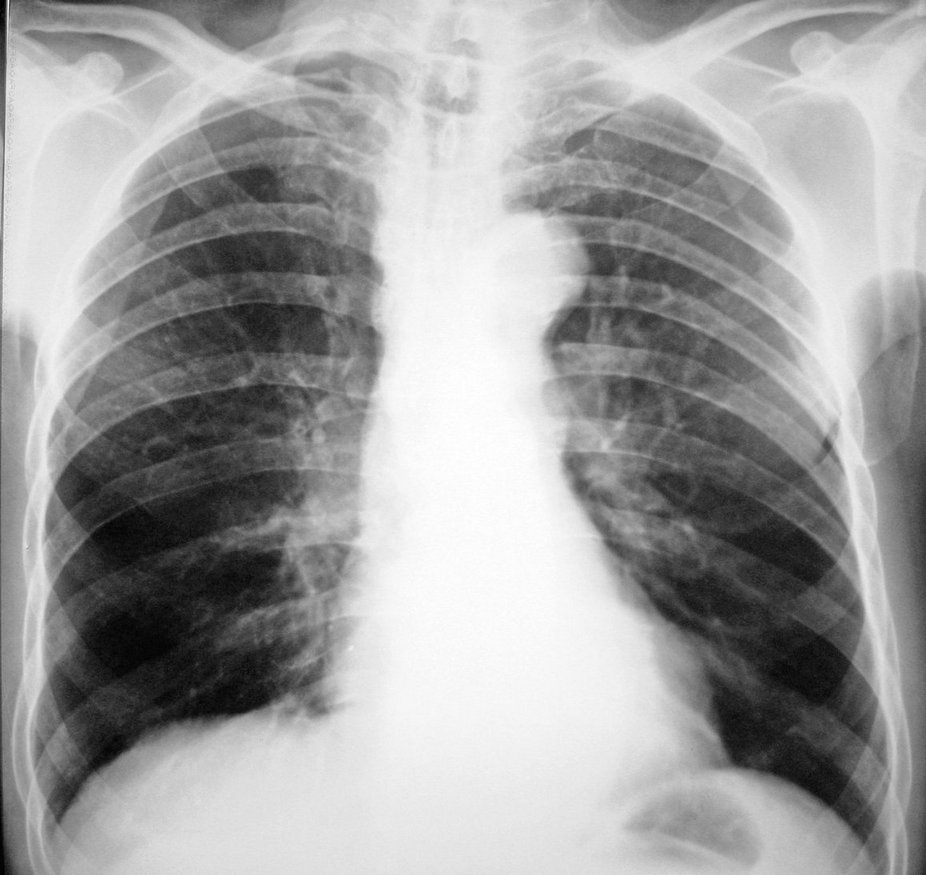

气管狭窄的发病较慢,直至气管腔被阻塞超过50%~70%时,才出现明显的自觉症状,也可由于继发性感染而使其进展加速,可在伤后1个月内发生严重的气管梗阻或窒息。